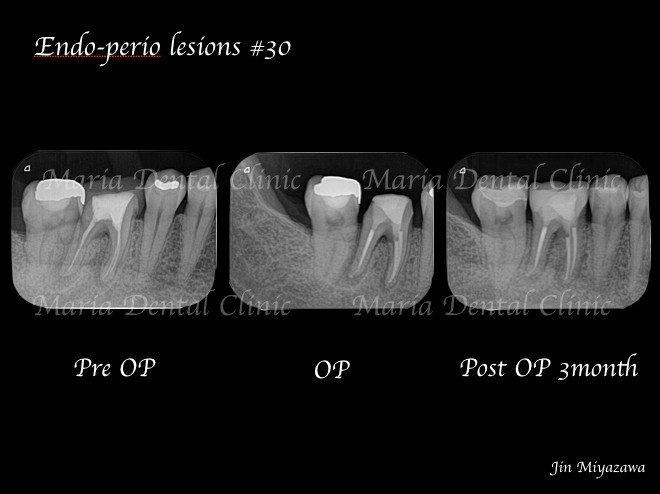

3ヶ月後のレントゲン撮影にて根尖病変の縮小、ならび違和感の消失を確認。今後最低2年間の経過観察(1年に1回)を行い、根尖周囲組織の治癒を確認していく。

今回は歯内歯周病変という、重篤な症状の治療経過を書かせていただきました。

_レントゲン画像術前術後の比較.jpg)

歯内歯周病変とは、歯の内側(根管内)のトラブルと歯の周囲組織のトラブルが併発することを言います。この場合、歯内療法と歯周病治療、両方からのアプローチを必要とする為、確実な診査、診断、そして治療が予後を左右します。

歯内歯周病変は限局的な歯周ポケットを併発するため、歯根破折と誤診されやすい病気です。当院の精密根管治療を希望し来院される多くの患者様が、他院にて「歯根破折」と診断されたが抜歯せず歯を残したいと望まれており、実際に精密根管治療を施すことで多くの歯が残せているのも事実です。